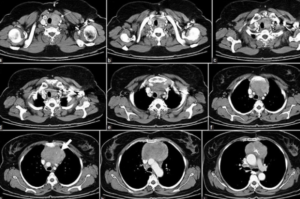

Фото КТ легких

Инфильтративный туберкулезЕдиничный цилиндрический бронхоэктаз (бронхит)